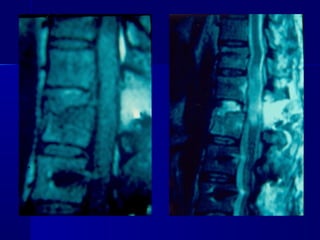

 AANN.. PPEERR..

 FF –– 2222 yyrrss

 FFaallll

 LLeevveell :: TT1122

 TTyyppee :: AA33..33

 AA..SS..II..AA.. :: EE